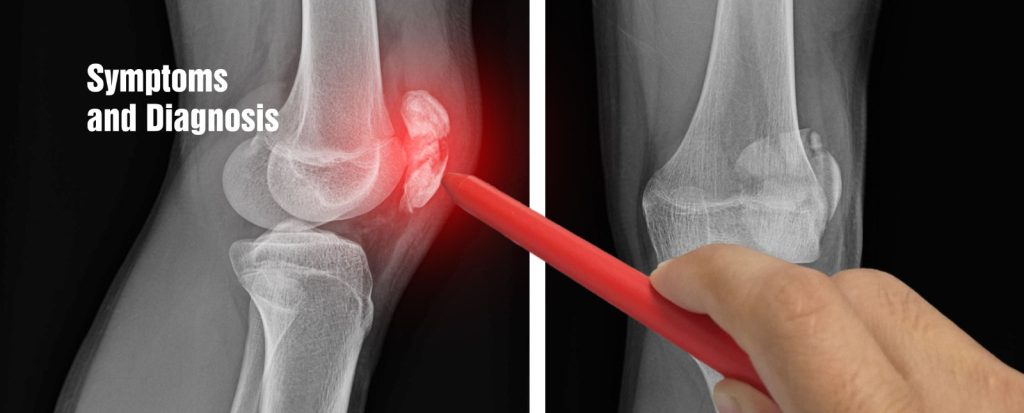

Symptoms and Diagnosis

Identifying knee implant allergies can be challenging. This is because symptoms may overlap with regular post-surgical discomfort. Patients who have undergone knee implant surgery should remain vigilant for certain symptoms. These are knee pain, swelling, warmth around the knee, and difficulty bearing weight. If any unusual symptoms arise, patients should contact our medical team for evaluation.

Healing Hospital’s orthopedic experts use advanced diagnostic techniques. These tests include patch testing, blood tests, and joint fluid analysis. Experts do the test to identify knee implant allergies and hypersensitivities. The patch test involves applying potential allergens to the skin to observe any adverse reactions. Blood tests measure immune responses to specific materials. While joint fluid analysis helps rule out other potential causes of the symptoms.